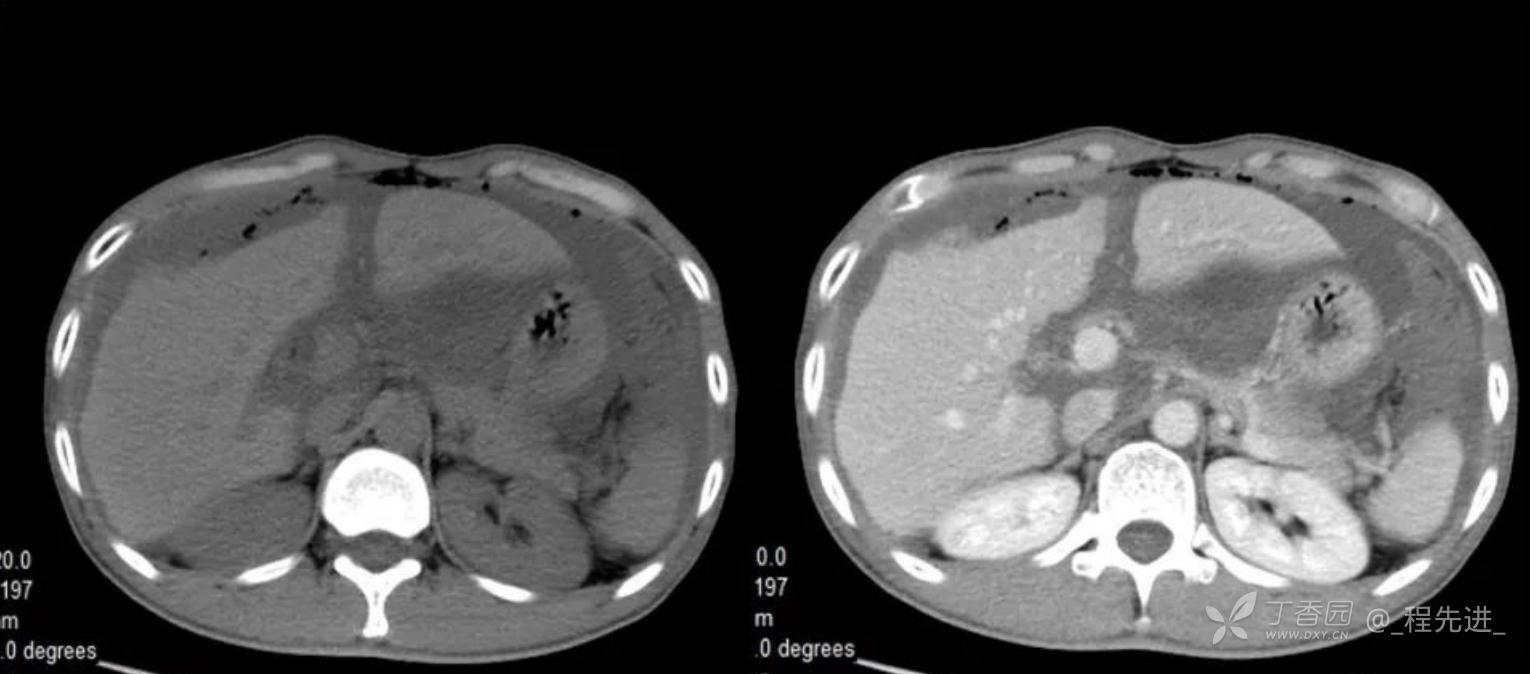

患者性别:男

患者年龄:46岁

主诉:腹胀10余天

现病史:患者10余天前无诱因腹胀,进食后加重,便后缓解,余无特殊

腹膜假黏液瘤 (5)